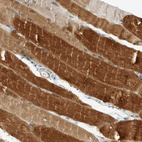

Immunohistochemistry analysis in human heart muscle and placenta tissues using HPA026900 antibody. Corresponding PLN RNA-seq data are presented for the same tissues.